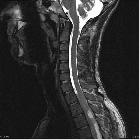

As astrocytomas arise from cord parenchyma (c.f. ependymomas that arise in the central canal), they typically have an eccentric location within the spinal cord.

They may be exophytic and even appear largely extramedullary. They usually have poorly defined margins. Peritumoral edema is present in ~40%. Intratumoral cysts are present in ~20% and peritumoral cysts are present in ~15%. Unlike ependymomas, hemorrhage is uncommon.

Reported signal characteristics include

- T1: isointense to hypointense

- T2: hyperintense

- T1 C+ (Gd)

- vast majority enhance (previously thought to be universally enhancing )

- usually patchy enhancement pattern